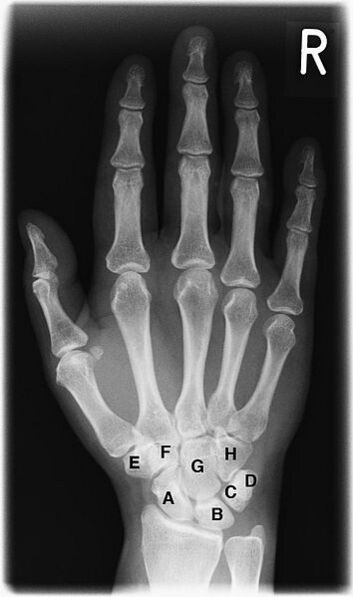

Костный возраст

Скелет кисти и лучезапястного сустава является наиболее удобным объектом для рентгенологического исследования развития костной системы человека[15]. На рентгенограмме кисти и лучезапястного сустава в прямой проекции видны ядра окостенения костей запястья, дистальных эпифизов лучевой и локтевой кости, наличие синостозирования эпифизов и диафизов. Сроки появления ядер окостенения и синостозирования зависят от пола и от возраста. Методика применяется для определения биологического возраста и его соответствия паспортному возрасту.

У доношенного новорожденного рентгенологическое исследование кисти и лучезапястного сустава в прямой проекции выявляет окостенение диафизов трубчатых костей, (развившееся из основных точек окостенения [или оссификации] начиная со второго месяца внутриутробного развития ребёнка), эпифизы трубчатых костей и кости запястья находятся на хрящевой стадии развития, поэтому на снимке не визуализируются. Иногда на рентгенограмме новорожденного выявляются точки окостенения головчатой и крючковидной костей, что дополнительно подтверждает доношенность новорожденного. В дальнейшем происходит последовательное появление ядер окостенения в костях запястья и эпифизах трубчатых костей. Наступление синостозирования эпифизов и диафизов трубчатых костей у мужчин происходит в возрасте 19—23 года, у женщин в 17—21 год. Современные исследования указывают на более ранние сроки синостозирования (закрытия хрящевых зон роста). Скелет лучезапястного сустава и кисти, состоящий из большого количества костей, претерпевает значительные возрастные изменения. Знание сроков и последовательности появления ядер окостенения позволяет профессионалам определить наличие эндокринной патологии и заболеваний других систем организма[15].